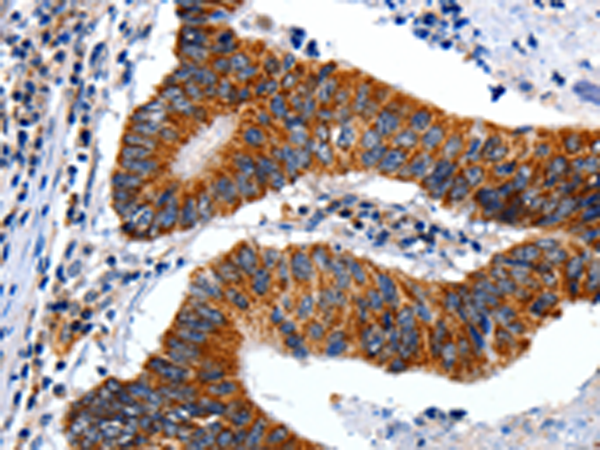

分类: 科研抗体货号: P10813别名: SAG; GP340; SALSA; muclin应用: IHC反应种属: Human, Mouse, Rat